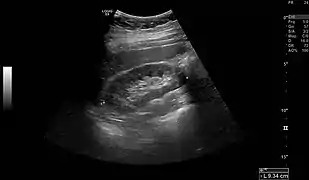

Normal adult right kidney as seen on abdominal ultrasound with a pole to pole measurement of 9.34 cm.

Imaging

Renal ultrasonography is essential in the diagnosis and management of kidney-related diseases.[43] Other modalities, such as CT and MRI, should always be considered as supplementary imaging modalities in the assessment of renal disease.[43]